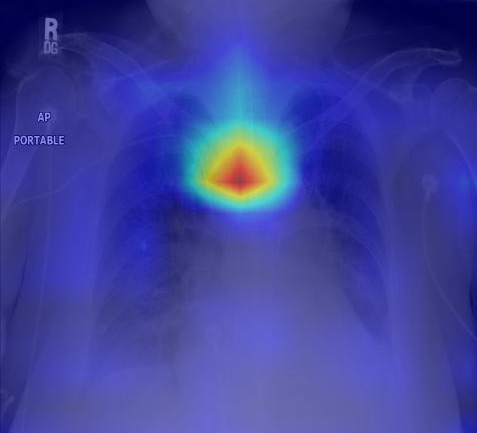

This platform brings together a collection of purpose-built digital resources developed to support targeted learning in radiology. Designed with clinical relevance and educational clarity in mind, each resource focuses on a specific area where accurate interpretation is essential and formal teaching is often limited or needs to be reinforced. These resources span multiple formats, and include advances in digital education, including videos, game-based learning, AI-enhanced image classification, interactive LLM chatbot, and microlearning material. Topics such as the assessment of medical lines and tubes on chest radiographs, or the identification of transient global amnesia on MRI, are approached through clinically relevant and user-focused content. By integrating imaging expertise with instructional design, this platform aims to complement traditional training with focused, accessible learning experiences that support both individual skill development and broader educational goals in radiology. It is intended for use by students, trainees, and clinicians in furthering their knowledge in radiology.